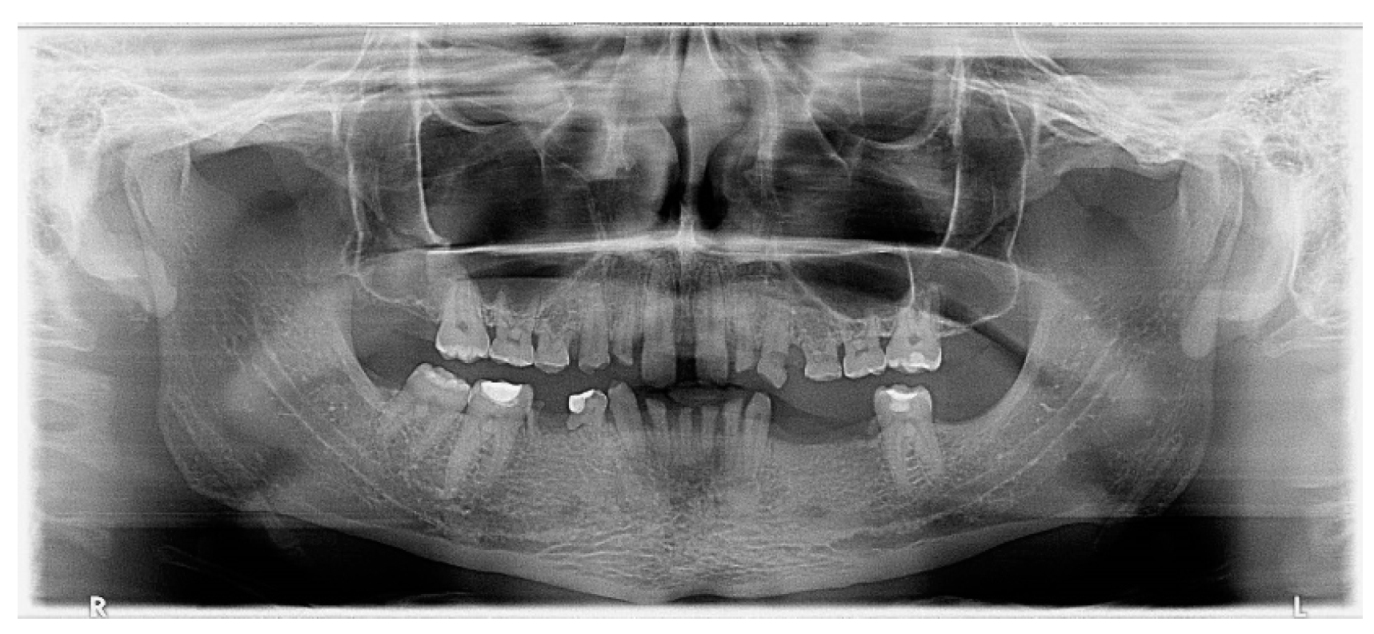

2. Case Presentation

- Preprosthetic orthodontic treatment